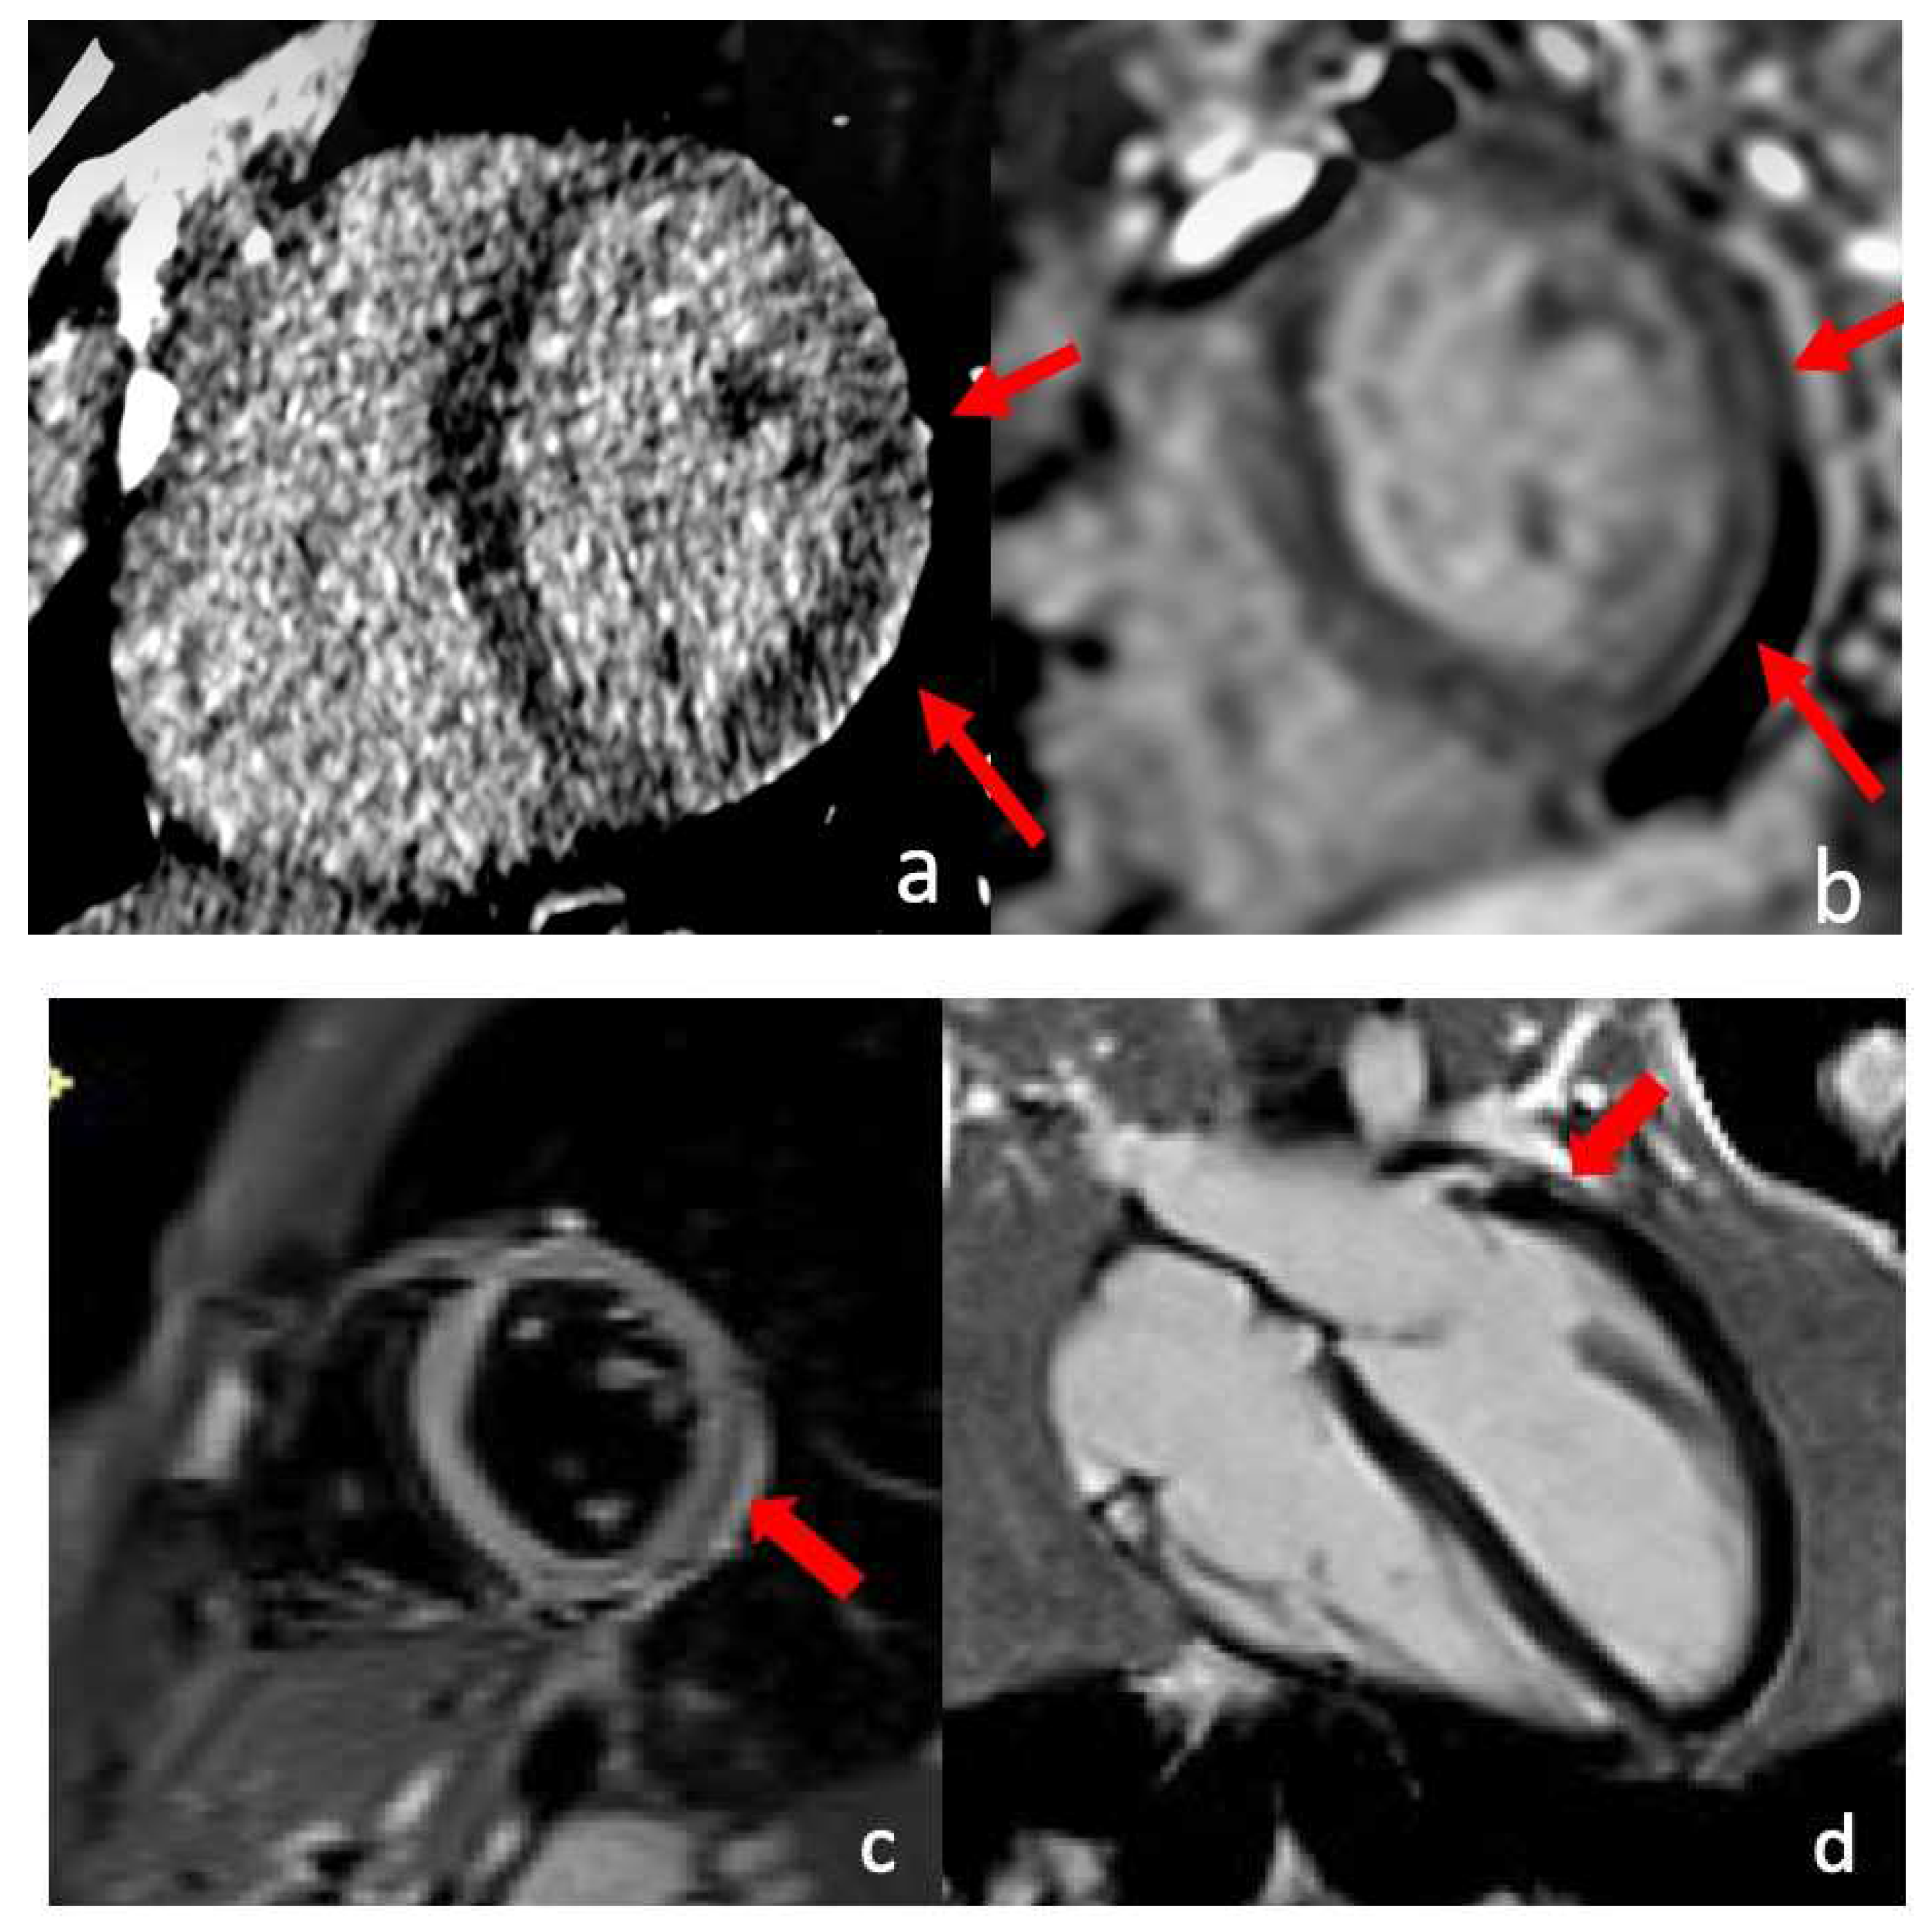

- Aslam, A.; Stojanovska, J.; Khokhar, U.S.; Weinberg, R.L.; Ganesh, S.K.; Labounty, T.; Sutton, N.R.; Patel, S. Spontaneous Coronary Artery Dissection: An Underdiagnosed Clinical Entity-A Primer for Cardiac Imagers. RadioGraphics 2021, 41, 1897–1915. [Google Scholar] [CrossRef]

- Marrazzo, G.; Palermi, S.; Pastore, F.; Ragni, M.; De Luca, M.; Gambardella, M.; Quaranta, G.; Messalli, G.; Riegler, L.; Pergola, V.; et al. Multimodality Imaging Approach to Spontaneous Coronary Artery Dissection. J. Clin. Med. 2022, 12, 154. [Google Scholar] [CrossRef]

- Tan, N.Y.; Hayes, S.N.; Young, P.M.; Gulati, R.; Tweet, M.S. Usefulness of Cardiac Magnetic Resonance Imaging in Patients with Acute Spontaneous Coronary Artery Dissection. Am. J. Cardiol. 2018, 122, 1624–1629. [Google Scholar] [CrossRef] [PubMed]

- Lionakis, N.; Briasoulis, A.; Zouganeli, V.; Dimopoulos, S.; Kalpakos, D.; Kourek, C. Spontaneous Coronary Artery Dissection: A Review of Diagnostic Methods and Management Strategies. World J. Cardiol. 2022, 14, 522–536. [Google Scholar] [CrossRef] [PubMed]

- Hayes, S.N.; Tweet, M.S.; Adlam, D.; Kim, E.S.H.; Gulati, R.; Price, J.E.; Rose, C.H. Spontaneous Coronary Artery Dissection: JACC State-of-the-Art Review. J. Am. Coll. Cardiol. 2020, 76, 961–984. [Google Scholar] [CrossRef] [PubMed]